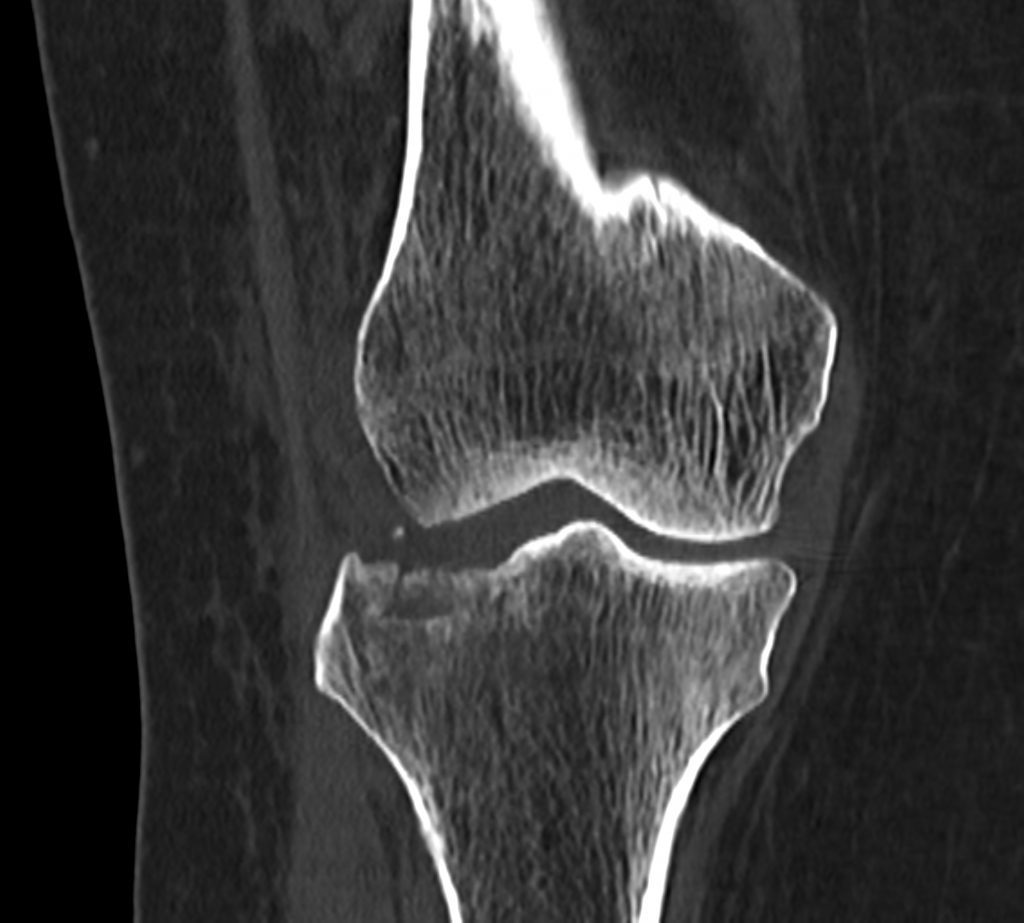

سي تي اسکن اسپيرال زانوي راست ( مولتي ديدکتور 16 با مقاطع ظريف و بازسازي هاي ساژيتال و کرونال و 3D):

– دفورميتي پلاتوي لترال تيبيا ناشي از depressed Fx و فرورفتگي در سطح مفصلي پلاتوي لترال

– نشانه هاي cortical Fx بدون جابجايي در کنديل لترال فمور

– loose body استخواني به ابعاد mm 2 x 3 در انترولترال مفصل زانو و

– افيوژن خفيف در مفصل زانو همراه با تورم نسج نرمي در اطراف آن

مشهود است .